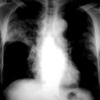

Fig. 1

Thin-section CT through the lower lung zones in a 43-yr-old woman with scrub typhus. There is thickening of the interlobular septa and small bilateral pleural effusions.